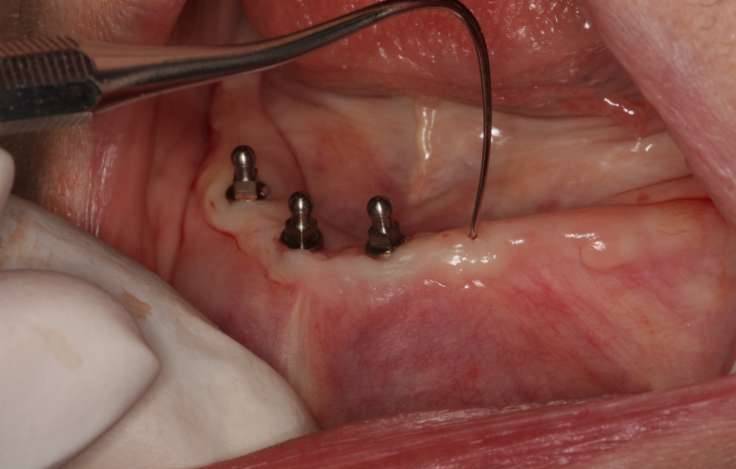

▼医生首先将她的牙全部拔掉,然后钻下铁块,过程中她的嘴巴里全都是血水。

▼这就是手术的过程。